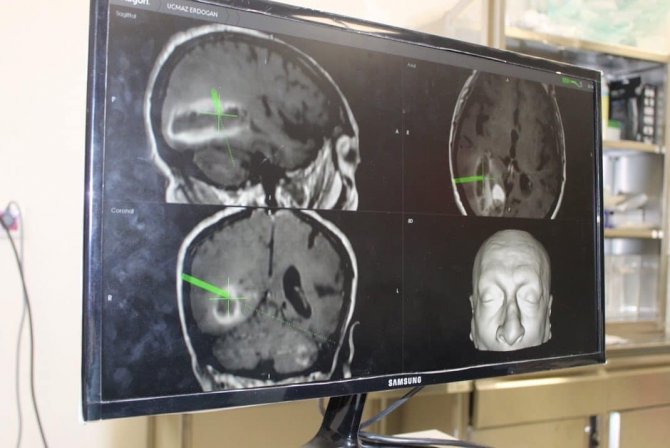

71 yaşındaki Erdoğan Uçmaz, şiddetli baş ağrısı, yürümede dengesizlik, görme keskinliğinde azalma ve ajitasyon şikayetleriyle Bilecik Eğitim ve Araştırma Hastanesi Acil Servisine başvurdu.Yapılan tetkikler sonucunda, beyninde tümör ve kanama tespit edilen hasta Uçmaz'a Tümör, Beyin ve Sinir Cerrahı Op. Dr. Mehmet Beşir Sürme tarafından nöronavigasyon sistemi eşliğinde gerçekleştirilen ve yaklaşık 4 saat süren başarılı bir operasyon gerçekleştirildi. Tümör tamamen çıkarılarak tanı için patolojiye gönderildi. Ameliyatında herhangi bir yan etki yaşanmayan hasta, ameliyat sonrası yoğun bakım ünitesinde 1 gün takip edilerek ertesi gün beyin cerrahisi servisine alındı. Şiddetli baş ağrılarının ve ajitasyon şikayetlerinin düzeldiği görülen hasta yaklaşık 1 hafta süren takip sonrası ek sorun izlenmemesi üzerine önerilerle taburcu edildi.

Nöronavigasyon sistemi hakkında bilgi veren Sürme, "Kitlenin sınırlarını net bir şekilde ortaya koyan, cerrahi planlamada hata payını minimale indiren, ameliyat süresini kısaltan, cerrahide güvenlik ve konfor sağlayan, ameliyat başarısını oldukça arttıran nöronavigasyon sistemi; günümüz cerrahi tıp teknolojisinin en gelişmiş cihazlardan biri olarak kabul edilmektedir. Hastanın beyin tümörünün nöronavigasyon sistemi ile çıkarılması ve beyin tümörü ameliyatı ilimizde ilk kez gerçekleştirilmesi nedeniyle ayrı bir önem arz etmektedir" diye konuştu.